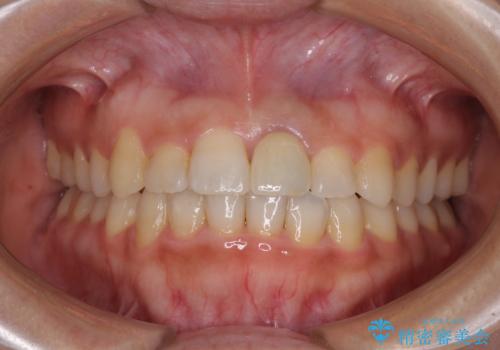

歯並びのがたつきを直したい ワイヤーは嫌 抜きたくない